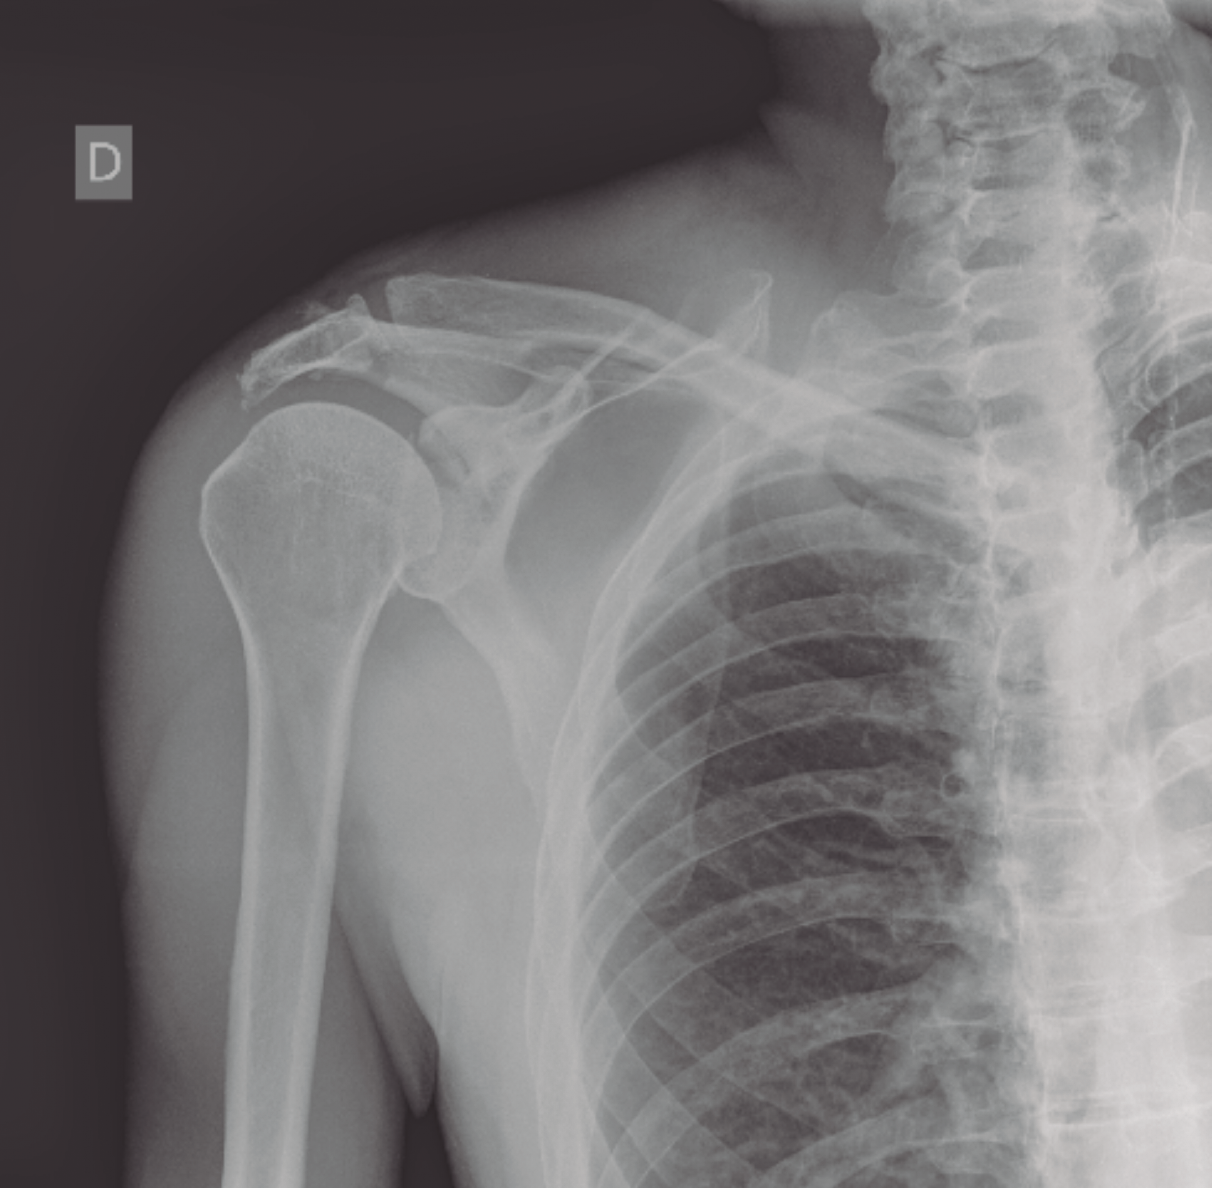

La radiología simple, única proyección anteroposterior, a su llegada a urgencias, muestra una fractura de la cavidad glenoidea que parece incluir la apófisis coracoides y una fractura del acromion sin desplazamiento significativo (Figura 1).

Figura 1. Radiografía anteroposterior tomada el día del traumatismo. Obsérvese la fractura de glenoides y del acromion.